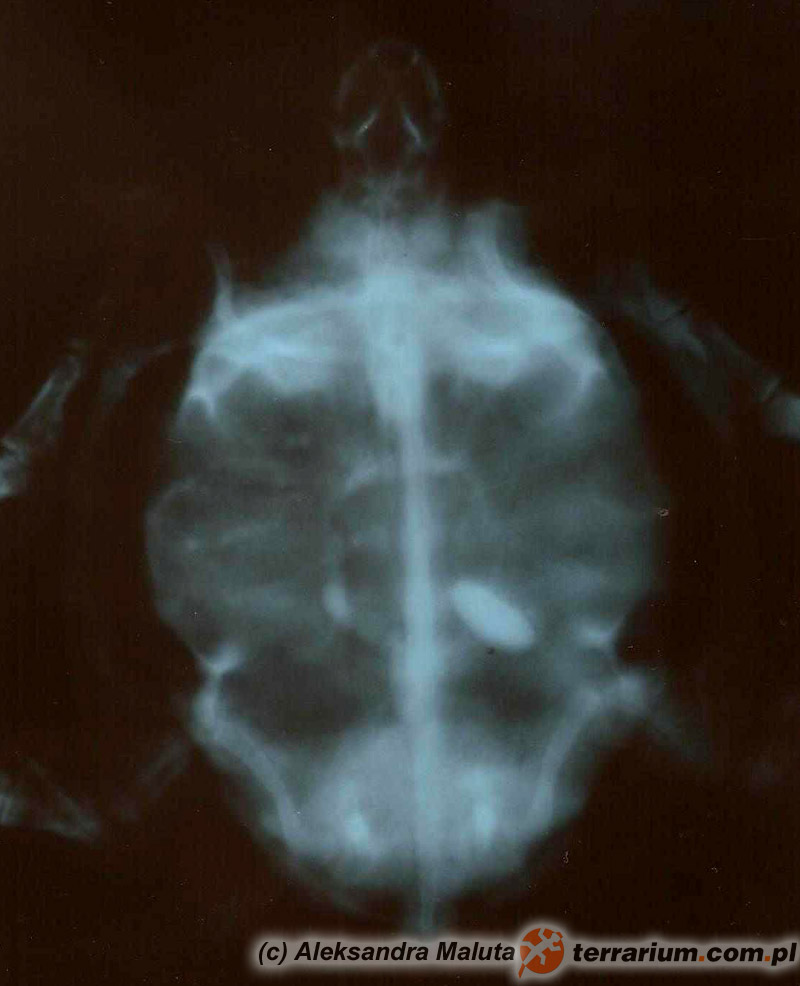

Żółwie to jedni z trudniejszych pacjentów, jeśli chodzi o diagnostykę. Obecność pancerza znacznie utrudnia badanie przez tzw. omacywanie, czyli palpację. Często potrzebne są badania dodatkowe, takie jak zdjęcie RTG, czy USG. Niestety w przypadku pierwszych, częstym problemem jest interpretacja wyniku, nawet specjaliści radiolodzy, opisujący RTG u psów i kotów mają kłopot z prawidłowym opisem badań wykonanych u żółwi, ze względu na ich szczególną anatomię. W obrazie RTG cień pancerza zaciera obraz narządów wewnętrznych i tylko osoba mająca doświadczenie w interpretacji obrazów rentgenowskich gadów i znająca ich anatomię może się pokusić o opis prześwietlenia, na którym brak ewidentnych zmian takich jak np. uwapnione jaja, bądź cieniujące ciało obce np. kamień.

W takiej sytuacji koniecznie należy wykonać zdjęcie RTG, a najlepiej dwa – w dwóch projekcjach, żeby dokładniej określić umiejscowienie ciała obcego oraz wypełnienie przewodu pokarmowego. Jeśli w badaniu rentgenowskim zostanie potwierdzona obecność ciała obcego (podobne objawy mogą dawać silne inwazje pasożytnicze), gadzina zazwyczaj jest kwalifikowana do operacji. Przed operacją powinny być wykonane badania biochemiczne krwi, aby dobrać odpowiednią do stanu pacjenta – najbezpieczniejszą narkozę. Podobne postępowanie diagnostyczne przeprowadza się w przypadku zaparcia jaj u żółwic. Pamiętajcie! Podanie oxytocyny, bez wcześniejszego zdjęcia rentgenowskiego określającego ilość jaj, ich wielkość, położenie oraz stan skorup, może przynieść więcej szkody niż pożytku. Nierzadko zdarza się, że jaja, które są zbyt duże i utknęły w kanale miednicznym, po podaniu hormonów cofają się… do pęcherza moczowego! A usunięcie ich z niego to prawdziwe wyzwanie i zegarmistrzowska robota.